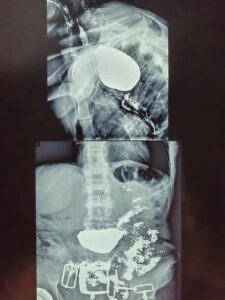

В Алматинской многопрофильной клинической больнице проведена уникальная операция пациенту 1954 года рождения, который более 30 лет страдал нарушением глотания. Диагноз – дивертикул Ценкера, редкая патология, встречающаяся примерно у 3,5% пациентов с заболеваниями пищевода.

Мужчина на протяжении десятилетий испытывал серьёзные трудности при приёме пищи. Последние годы состояние резко ухудшилось: пища застревала, приходилось самостоятельно надавливать на шею, чтобы она частично проходила в желудок. Остальное выходило наружу с рвотой. За последние 2–3 года пациент потерял около 20 кг и оказался на грани истощения.

Операцию провёл хирург Алматинской многопрофильной клинической больницы Айазбаев Нурбол Бейсенович. В ходе вмешательства удалось освободить пищевод в области шейного отдела и удалить расширенный участок.